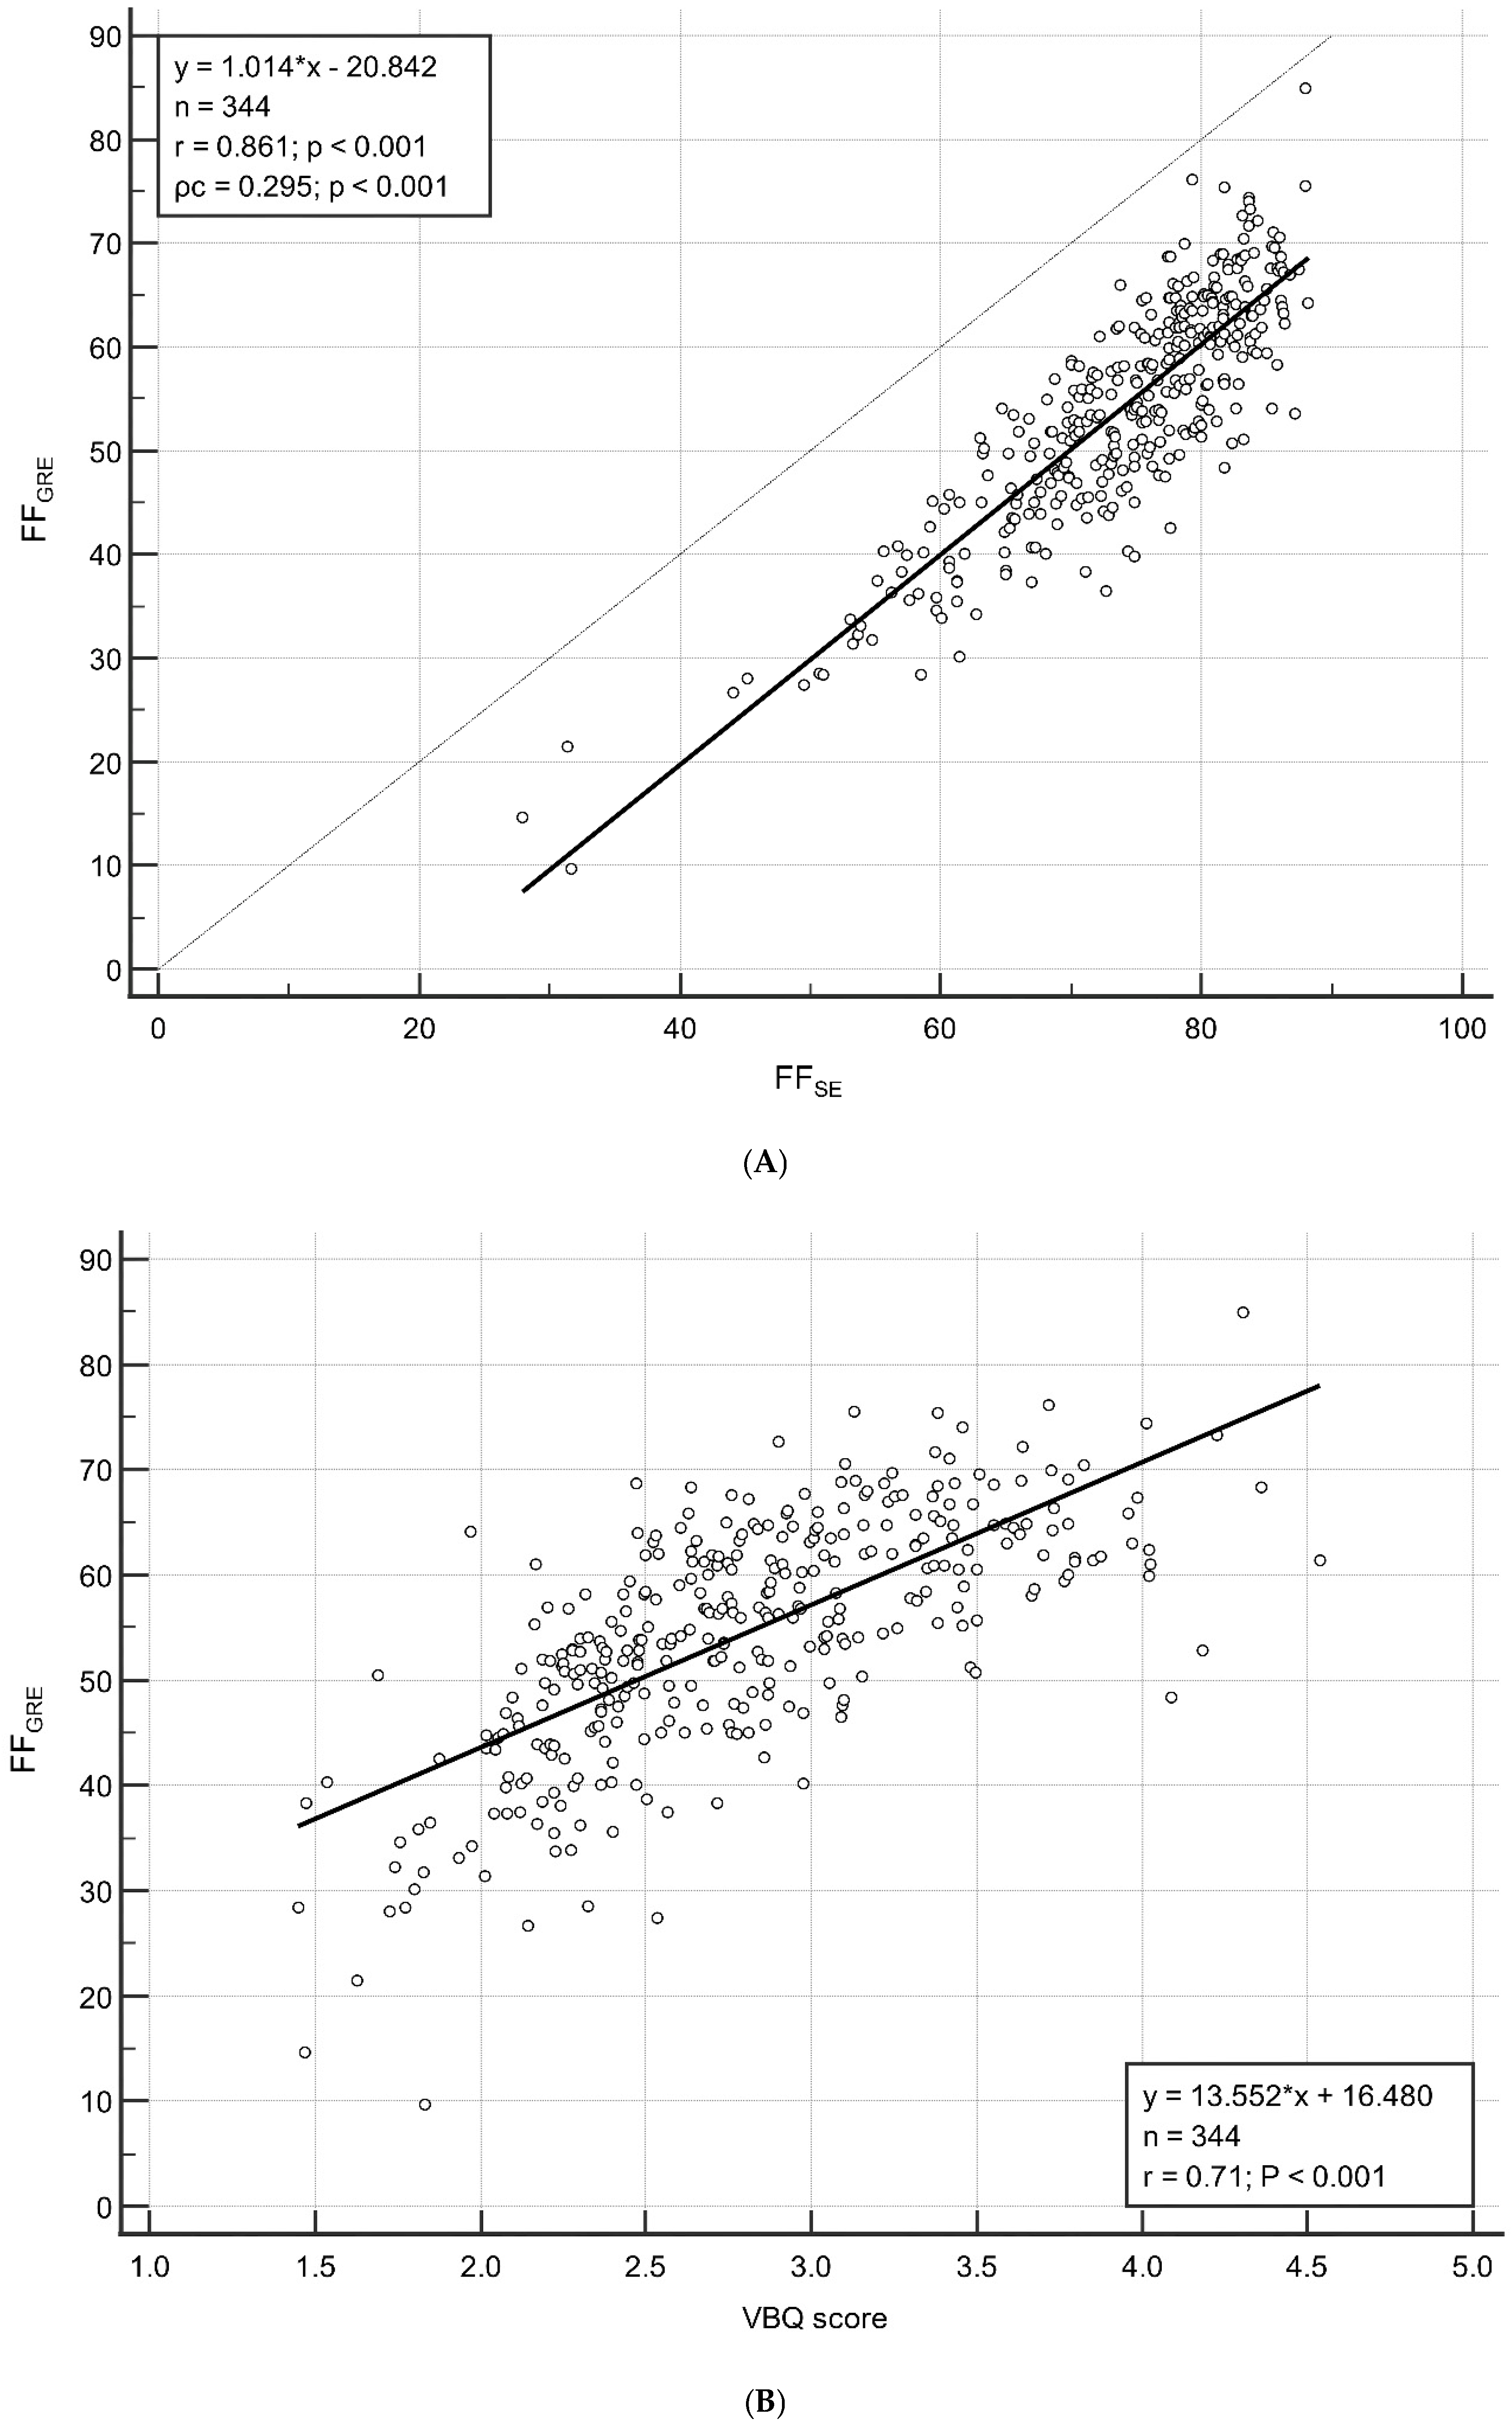

3.2. Correlation Between FFGRE and FFSE/VBQ Score

3.3. Correlation Between Age and FF/VBQ Score